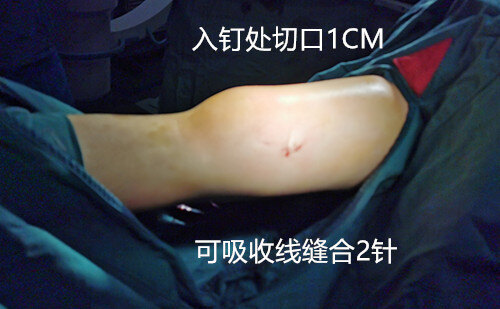

入院后,完善检查,我科采用了经典的牵引闭合复位弹性髓内钉内固定治疗,取的良好的复位效果。

闭合复位弹性髓内钉内固定治疗儿童股骨干骨折具有很多优点,尤其是手术微创,不需要切开复位,不只减少孩子的手术创伤和疼痛,而且具有微创,切口小,恢复快,住院时间短,取钉便捷等诸多优点。